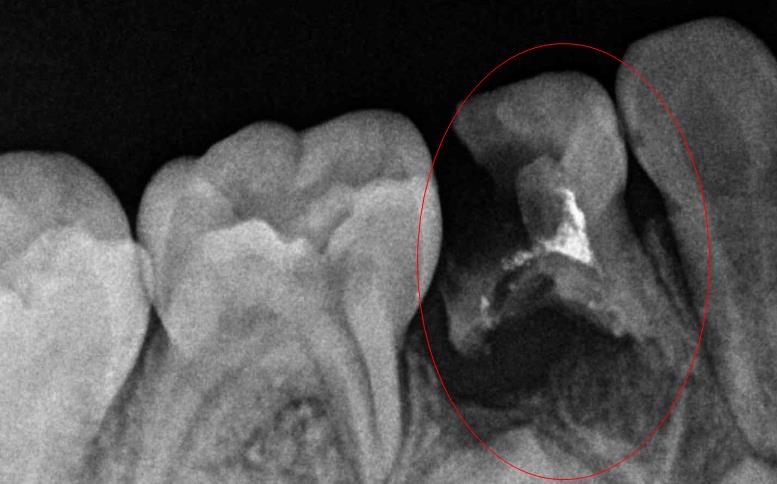

嚴(yan) 重齲壞的牙齒

蛀牙後怎麽(me) 判斷哪種是能補需要充填補牙的,哪種需要根管治療的,哪種無法保留需要拔掉的呢?這一般無法通過肉眼做出判斷的,需要到醫院拍片,檢查蛀牙實際齲壞的程度後才能確定詳細的治療方法。

沒有齲壞到牙神經,充填補牙就可以,齲壞到牙神經,根管治療可以保留牙齒,但是如果隻剩下殘根,而且沒法補牙治療保留的話,可能就需要拔除了。這是需要正規專(zhuan) 業(ye) 醫生來判斷的。